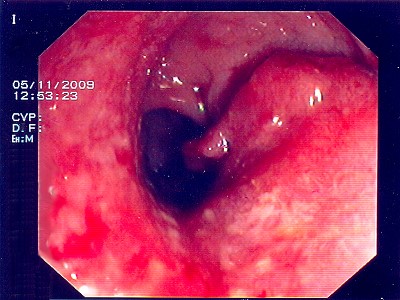

Abb. 2: Das Gebilde des oberen Mastdarmes, auch hier ist die Ent- fernung des Tumors mittels Darmspiegelung nicht mehr möglich. Abb. 2: Das Gebilde des oberen Mastdarmes, auch hier ist die Ent- fernung des Tumors mittels Darmspiegelung nicht mehr möglich.